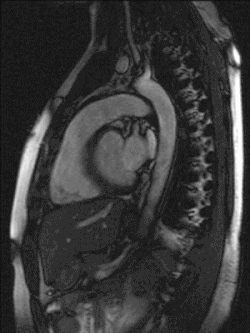

Das Herz liegt innerhalb des Herzbeutels (Perikard) im Mediastinum: Seitlich grenzen, getrennt durch parietale und viszerale Pleura (Brustfell), die linke und rechte Lunge an das Herz. Unten sitzt das Herz dem Zwerchfell auf, das mit dem Herzbeutel verwachsen ist. Oberhalb teilt sich die Luftröhre (Trachea) in die beiden Hauptbronchien (Bifurcatio tracheae), von denen der linke vom Aortenbogen überquert wird. Unterhalb dieser Aufteilung befindet sich der linke Herzvorhof. Wenn dieser krankhaft vergrößert ist, kann das zu einer Spreizung der Hauptbronchien führen, was sich im Röntgenbild als vergrößerter Winkel zwischen den Bronchien darstellt. Der linke Vorhof steht außerdem nach hinten in direktem Kontakt mit der Speiseröhre. Vor dem Herzen befindet sich das Brustbein (Sternum), im oberen Bereich liegt es vor den abgehenden großen Gefäßen. Zwischen Brustbein und Herz liegt der Thymus.

Das Herz liegt also praktisch direkt hinter der vorderen Leibeswand in Höhe der zweiten bis fünften Rippe. Die Herzbasis oben reicht nach rechts etwa zwei Zentimeter über den rechten Brustbeinrand hinaus. Unten kommt die Herzspitze knapp an eine gedachte senkrechte Linie heran, die durch die Mitte des linken Schlüsselbeins verläuft (linke Medioklavikularlinie).

Anatomie

Die Gestalt des Herzens gleicht einem abgerundeten Kegel, dessen Spitze nach unten und etwas nach links vorne weist. Das Herzvolumen entspricht ungefähr dem Volumen der geschlossenen Faust[19] des betreffenden Menschen. Das Herz sitzt beim Menschen in der Regel leicht nach links versetzt hinter dem Brustbein. In seltenen Fällen ist es nach rechts versetzt (die sogenannte Dextrokardie – „Rechtsherzigkeit“), meist bei Situs inversus (also bei spiegelverkehrter Organanordnung).